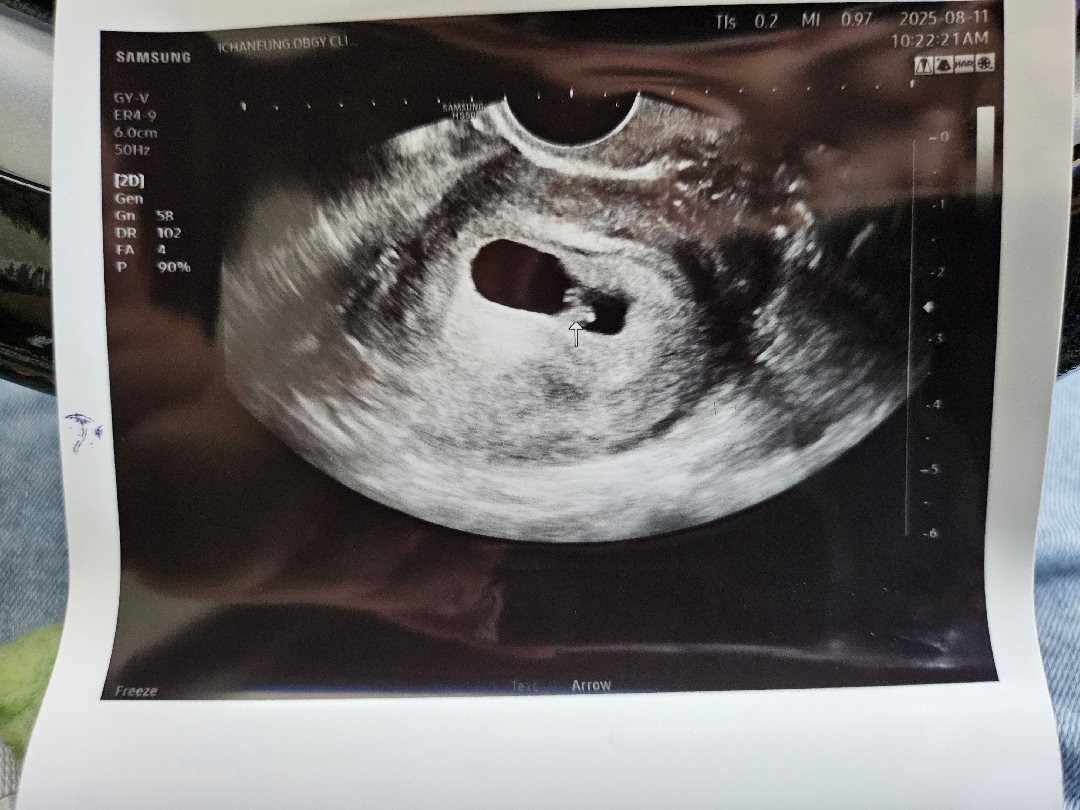

빌리주기로 7주3일 아기 크기

크기는 모르겠는데 사진상 작아보여서요. 배 초음파 볼때 착상불안하다 하셨거든요. 질초음파 보니 아기 심장 뛰는데 아직은 심박수가 우렁차지는 않네요ㅠㅠ 첫째때는 뭘해도 잘 컸는데 둘째는 다르네요